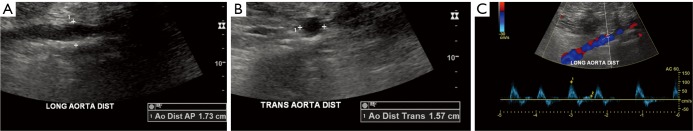

Figure 1.

Normal AAA screening ultrasound examination. A 70-year-old male former smoker referred for AAA US screening. (A) Longitudinal and (B) transverse grayscale sonographic images show normal caliber of the distal abdominal aorta (<3 cm). Note that measurements are made from outer wall to outer wall; (C) Doppler evaluation demonstrates an expected aortic spectral tracing with normal color flow. AAA, abdominal aortic aneurysm.